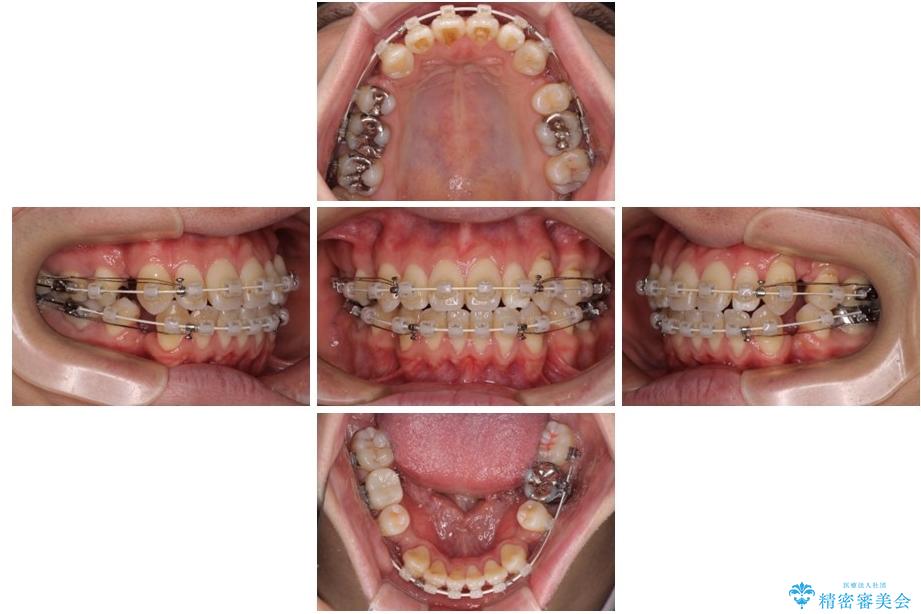

治療後

• 口元の突出感を改善!目立ちにくいワイヤー矯正で自信を持てる自然な横顔に 治療後画像